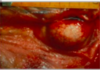

Endocardite valvulaire

Multiples masses volumineuses siégeant au niveau de l’endocarde valvulaires, d’aspect bourgeonnant « en chou fleur » de couleur rouge-jaunâtre.